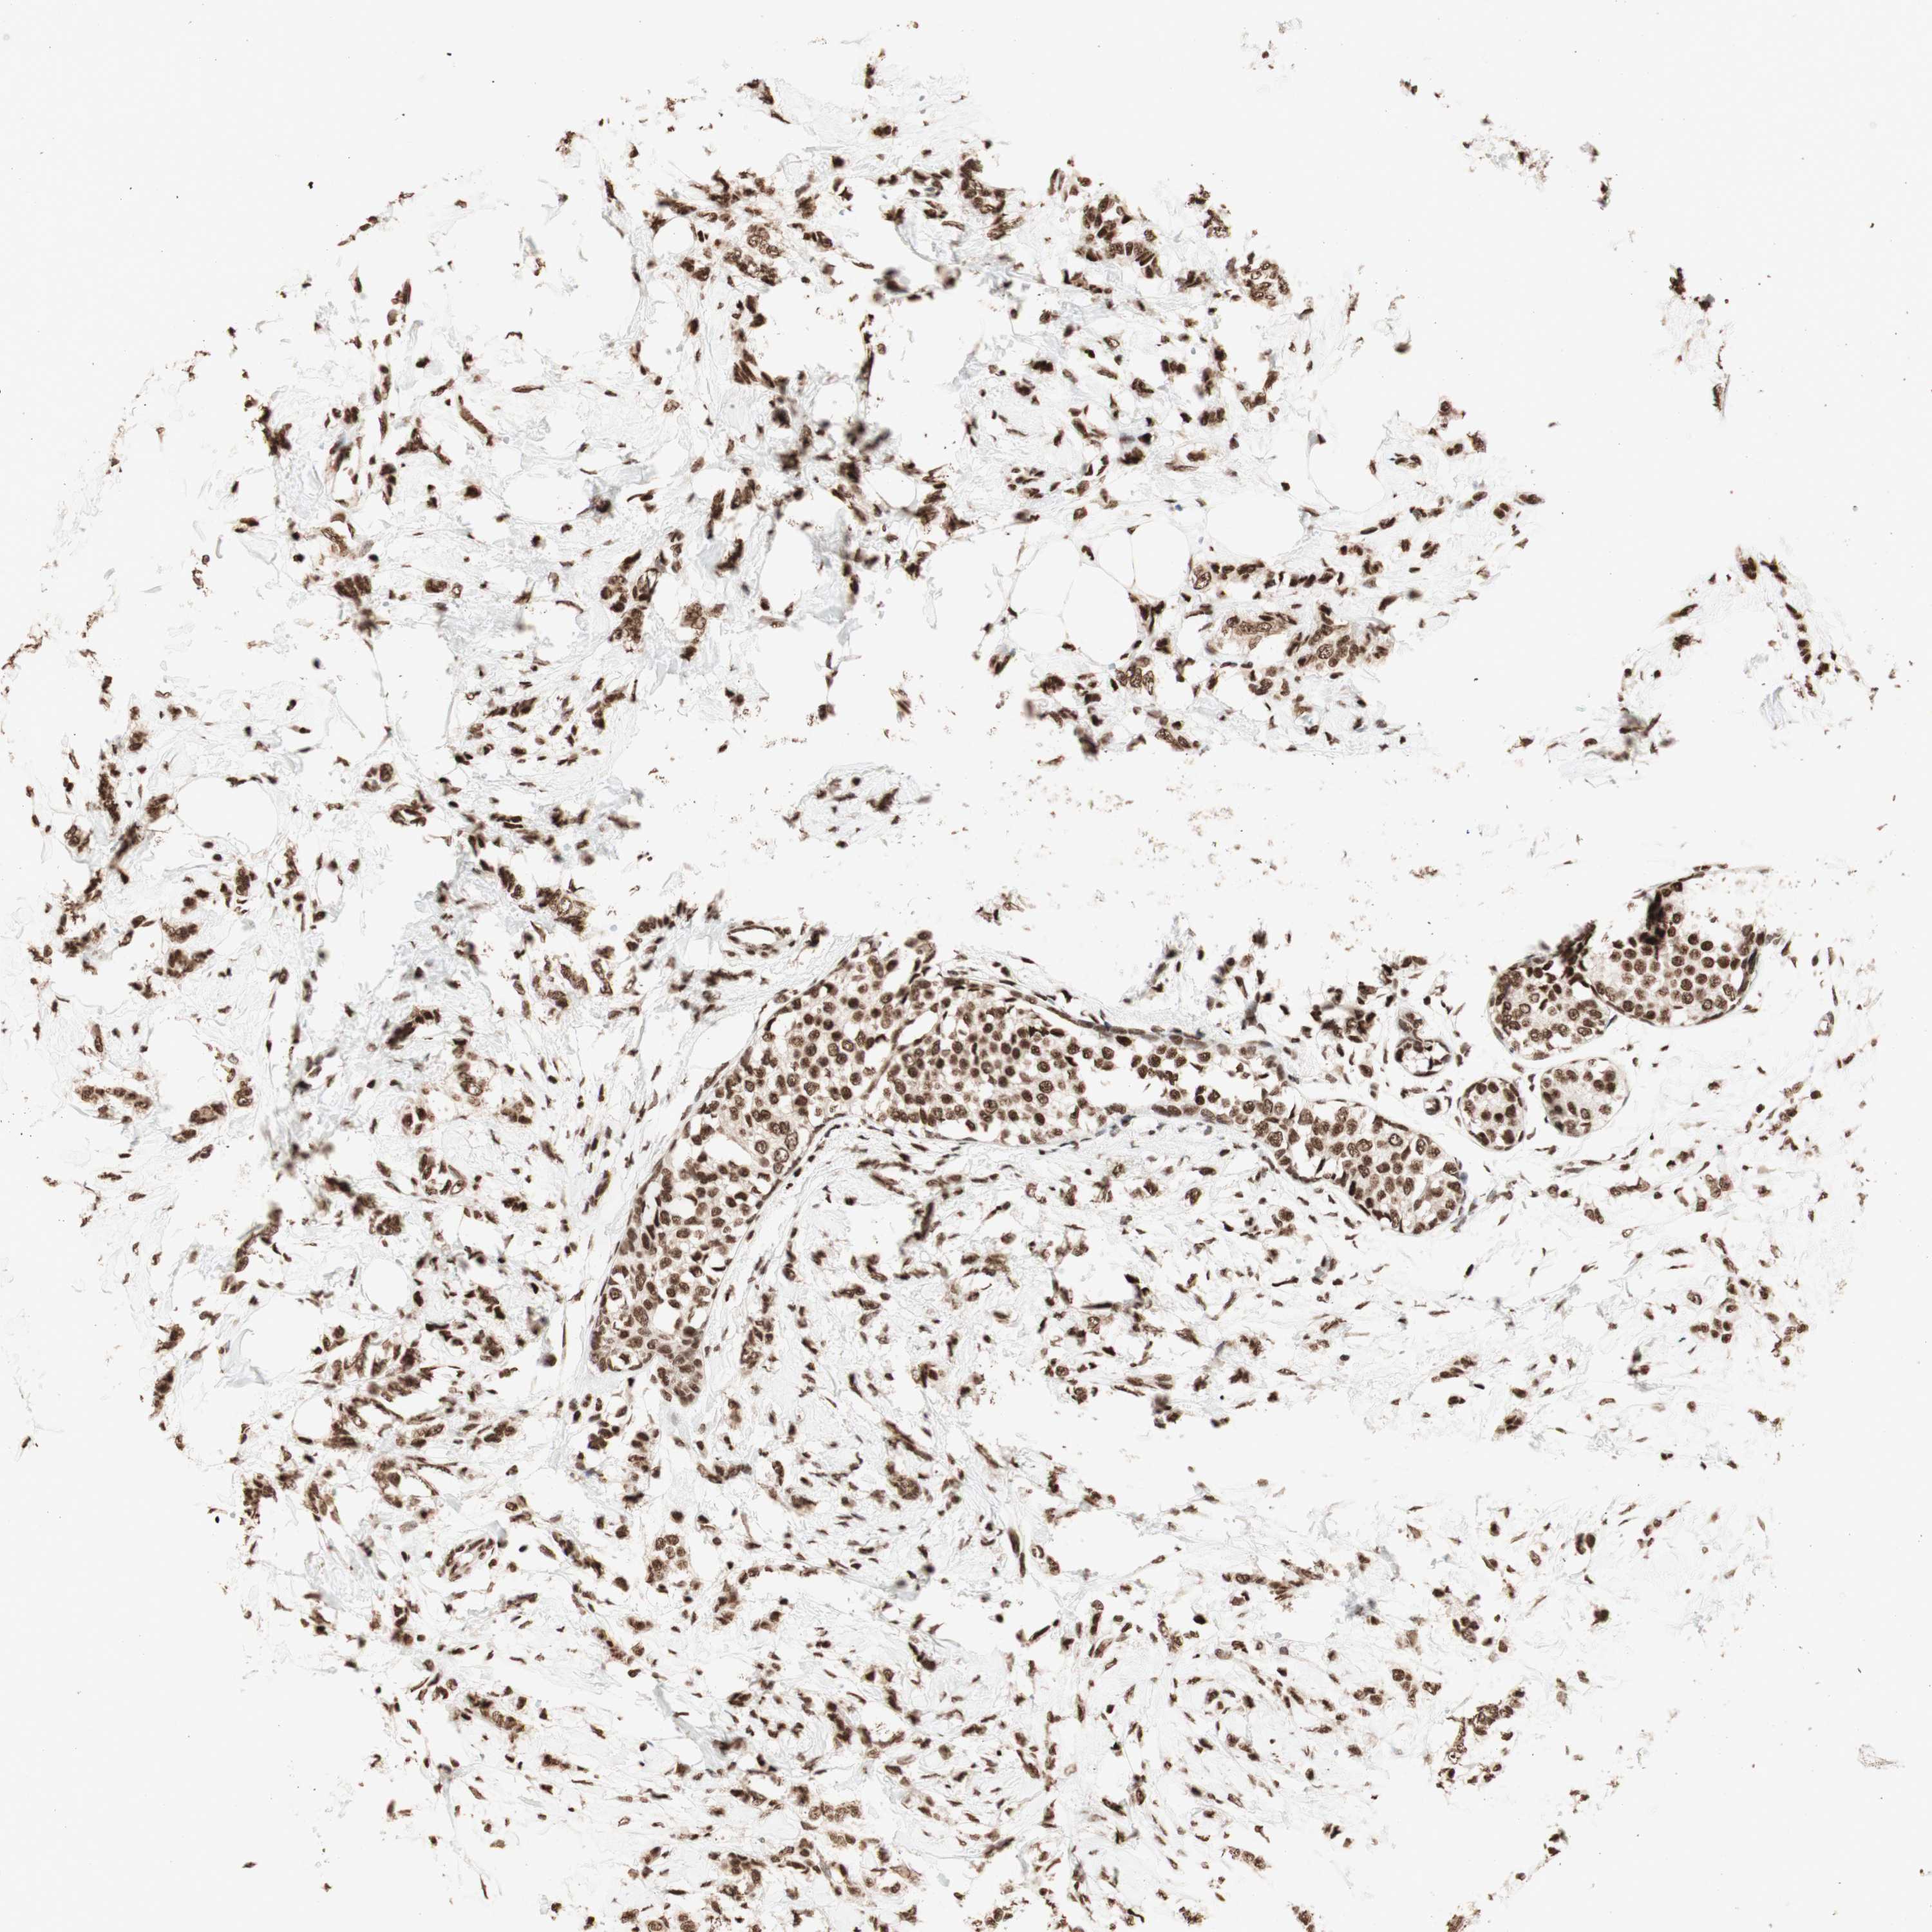

BRCA TCGA BRCA VALIDATION PROTEIN EXPRESSION

ANTIBODIES

AND

VALIDATION